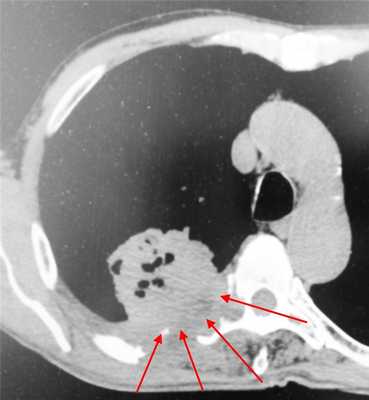

Пример контактного распространения опухоли: мезотелиома плевры, прорастающая в верхнюю легочную долю и грудную стенку. Спиральная компьютерная томография (МСКТ).